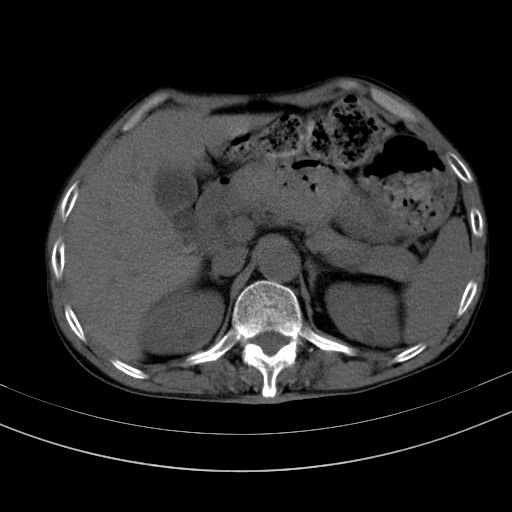

以下是引用dyqct在2010-1-9 17:56:00的发言:[br]考虑:1.双肾囊肿,左肾积水结石、旋转不良。[br] 2.右侧腹直肌血肿或纤维瘤。[br]肠道准备不好。做个增强。